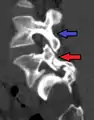

Anterolisthesis L5/S1. Blue arrow normal pars interarticularis. Red arrow is a break in pars interarticularis

Computed Tomography (CT)

Computed tomography can be helpful in evaluating bony vertebral abnormalities, such as fractures.[33] This can be helpful in determining if the fracture is a new, old, and/or progressing fracture.[33] CT use in spondylolisthesis evaluation is controversial due to high radiation exposure.[34]